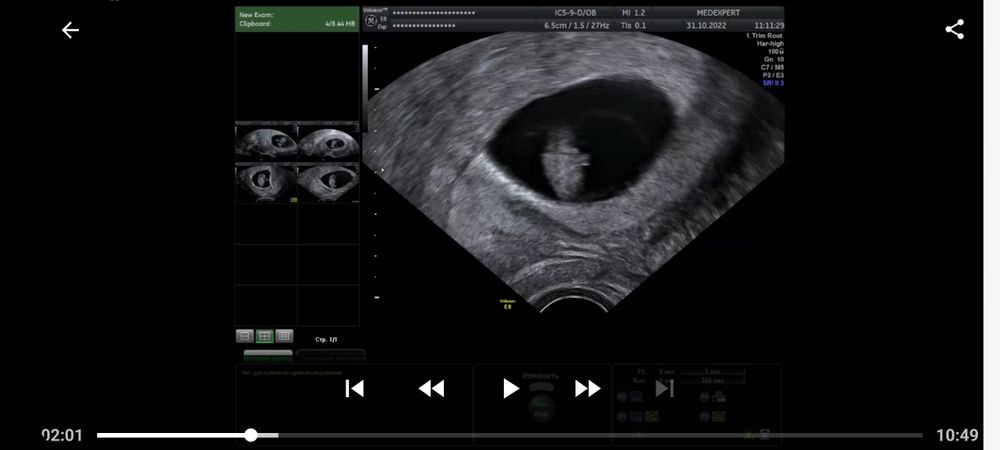

Ретрохальная гематома и мягкая шейка 9 недель беременности

9 недель и 3 дня срок. Сегодня сделала узи, по причине того, что в прошлый раз была отслойка 11×3мм (заключение прикладываю). В результате сегодня имеем прогрессирующую отслойку 27×3мм. Помимо этого шейка матки очень мягкая и губы свободно двигаются при перемещении датчика. Иногда тянет живот, не сильно, как перед месячными, только намного слабее. Выделения по цвету немного желтоватые, но не постоянно, а раз за несколько дней. А так, нормальные по цвету, без запаха. Кровяных или коричневых выделений нет. Прием у акушера-гинеколога только завтра. Приговор врача-узи заставляет нервничать и переживать, но пытаюсь отвлечься и успокоиться, была озвучена угроза прерывания беременности. Приехала домой и соблюдаю постельный режим до завтрашнего дня. Встаю только по крайней необходимости (туалет, покушать). Из препаратов ничего не принимаю, только витамины Элевит первый триместр. Как мне вообще вести себя в данной ситуации до приема врача? Чего бояться и при каких ситуациях вызывать скорую. Короче я напугана.